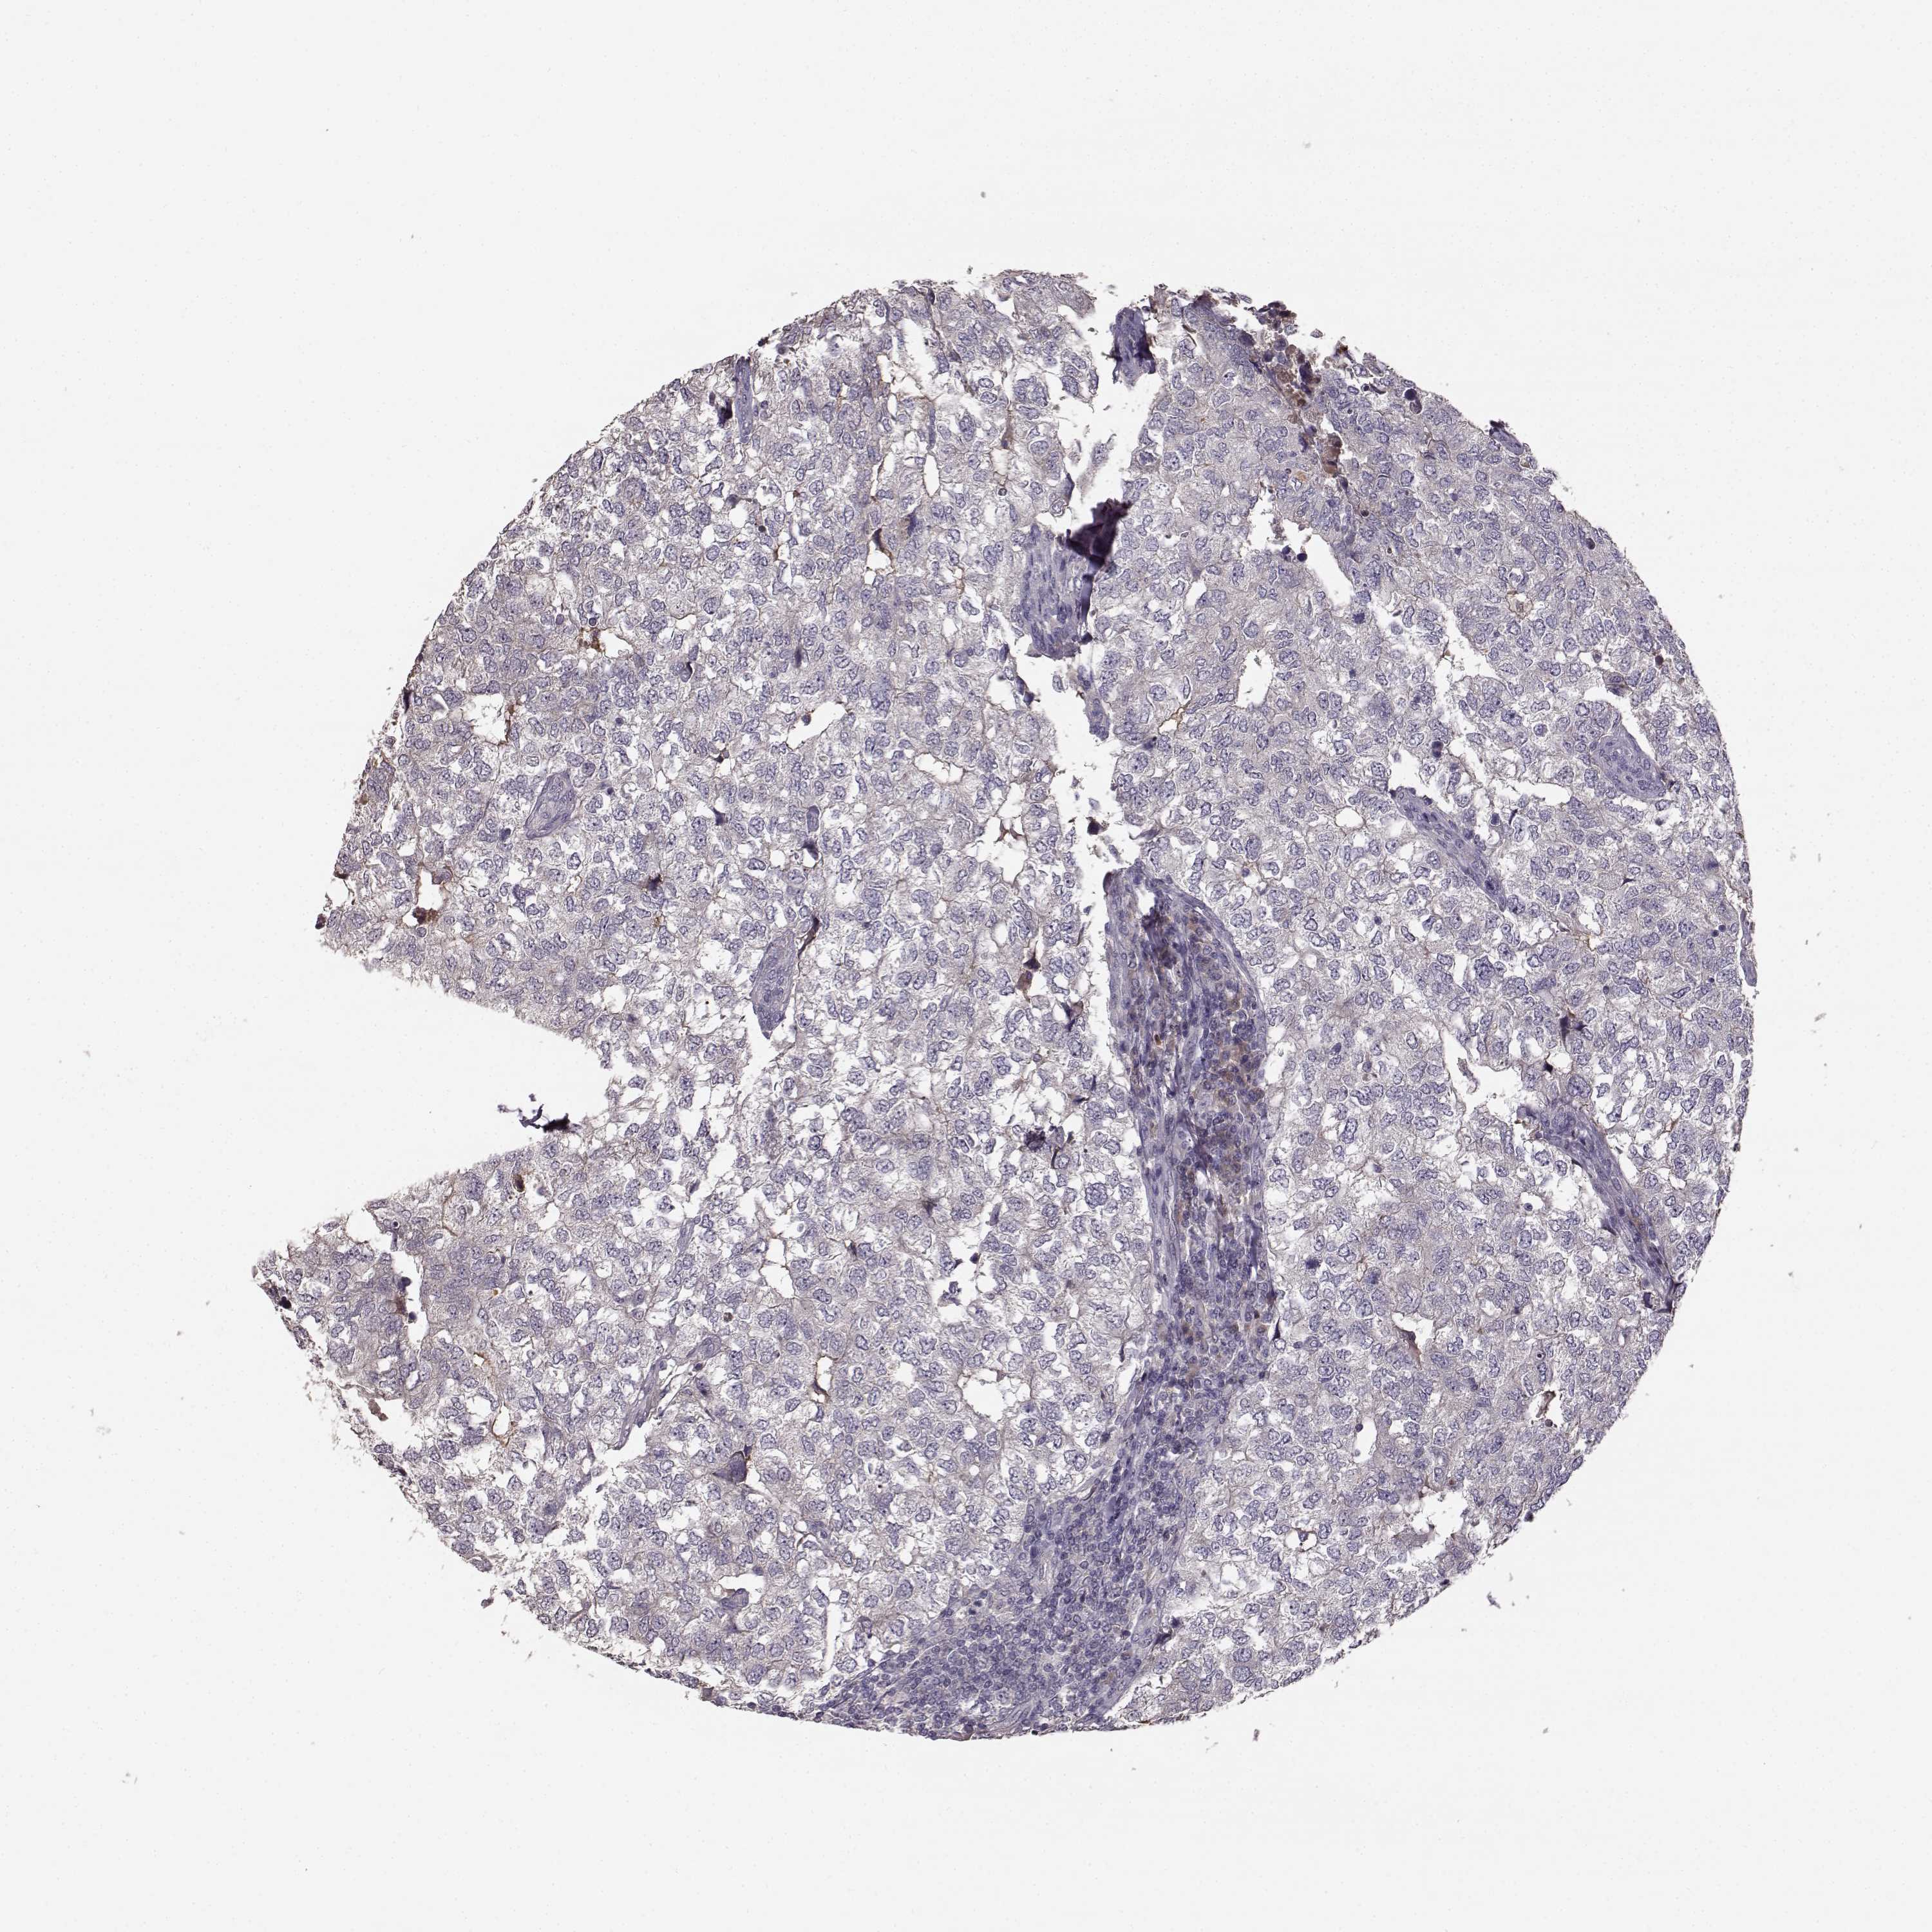

CANCER BREAST CANCER Show tissue menu

BRCA TCGA BRCA VALIDATION PROTEIN EXPRESSION